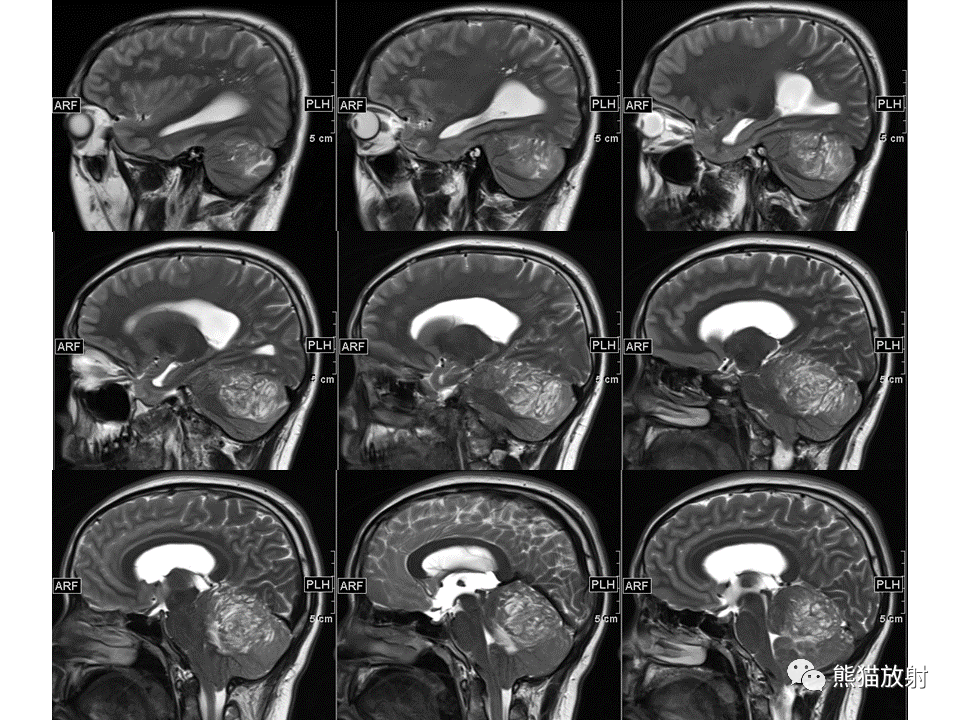

【PPT】小脑发育不良性神经节细胞瘤 VS 成人型髓母细胞瘤-1